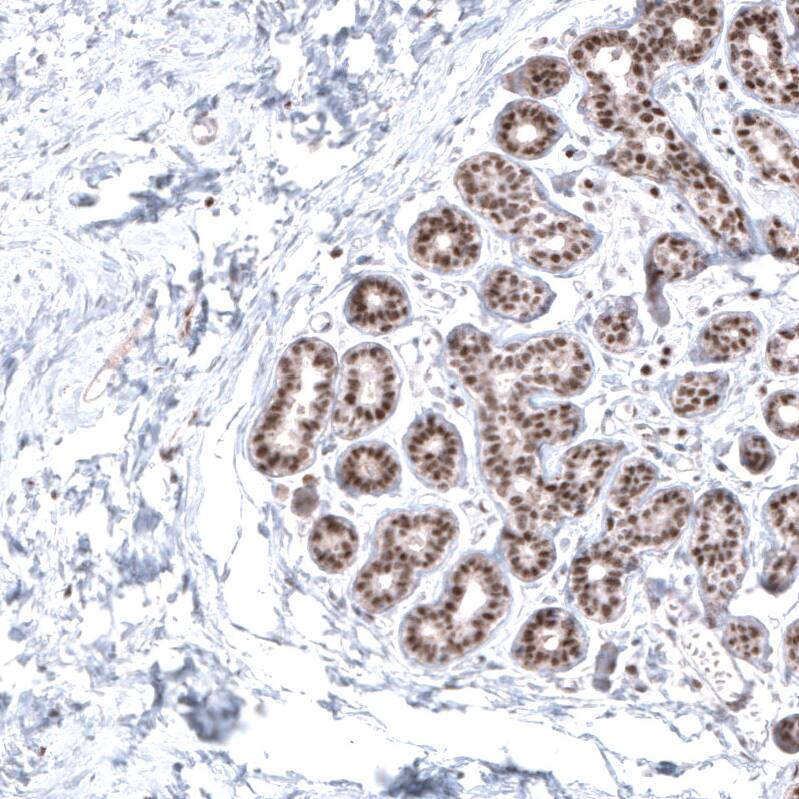

Staining of human breast shows moderate to strong nuclear positivity in glandular cells.